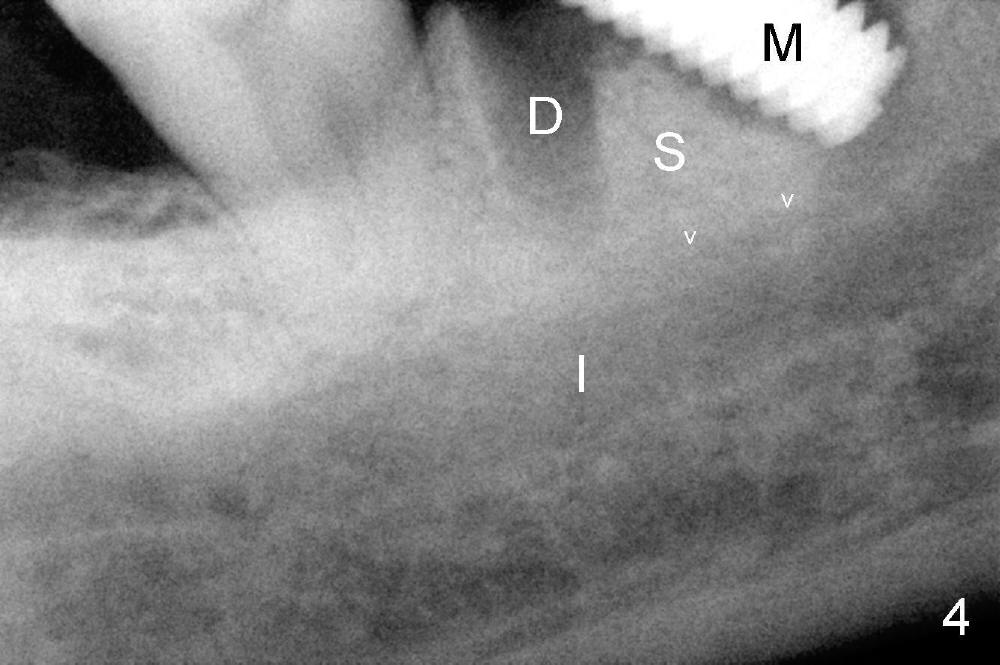

The tooth #30 of a 64-year-old man has endo failure with large radiolucency in the mesial socket (Fig.1 (PA), 2 (CT)).  The tooth is nonsalvageable.  The mesial lesion is closer to the inferior alveolar nerve (I/IAN) than the distal apex.  In addition, there is a connection (Fig.1,2 arrowheads and Fig.2 insert pink dashed line) between the mesial lesion and the nerve.  What is the connection, as related to extraction and immediate implant?

There are three potential spaces for the immediate implant: the mesial and distal sockets and the septum.  First at all, the tooth should be extracted with curettage of granulation tissue from the mesial apical lesion.  The latter turns out to be difficult, since the bottom of the mesial socket has abrupt transition into a narrow neck, which look and feels like the IAN.  To determine the depth of the lesion relative to the IAN, PA is taken (Fig.3) without too much information.  When a radiopaque material in placed in the mesial socket (Fig.4 M), the lesion has apparently not extended to the IAN.  Curettage of the remaining granulation tissue is now an easy task.  Finally bleeding comes from a small hole, as indicated by arrowhead.  Therefore the special structure is a branch of the inferior alveolar vessels.

As to where to place an implant, we try to engage the largest tap (8 mm in diameter) into the mesial socket without binding. The buccal plate of the mesial socket is missing.  It is risky to extend osteotomy in the mesial socket.  Besides, the septum (Fig. 4 S) is not as tall as the distal socket (D).  It appears that the distal socket is the safest place to place an implant.  Furthermore, no drill is used for distal osteotomy.  Instead two osteotomes (3.5x15 and 4x15 mm tapered osteotomes) are used to expand the distal socket with intention to push the septum mesially.  Since the bone density is high, the osteotomes seem not to work as effectively as expected.  Then a 4.5x17 mm tap is placed at the depth ~ 14 mm with stability (Fig.5).  Finally a 5x14 mm tissue-level implant is placed with insertion torque >60 Ncm (Fig.6).  Allograft is placed in the mesial socket and buccal aspect of the distal socket, followed by insertion of collagen plug and membrane (Fig.7).  After insertion of an abutment (Fig.8 (taken 6 days postop) *), perio dressing (P) is applied to cover the wound.  There is no postop paresthesia.